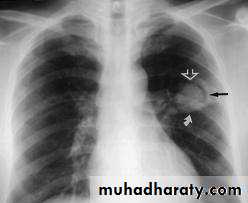

Inhaled Aspergillus may lodge and germinate in areas of damaged lung tissue forming a fungal ball or aspergilloma.The upper lobes are most frequently involved, and fungal balls readily form in tuberculous cavities..

#often asymptomatic, and are identified incidentally on chest X-ray.The fungal ball produces a tumour-like opacity on X-ray (presence of a crescent ),they may cause recurrent haemoptysis

# HRCT is more sensitive